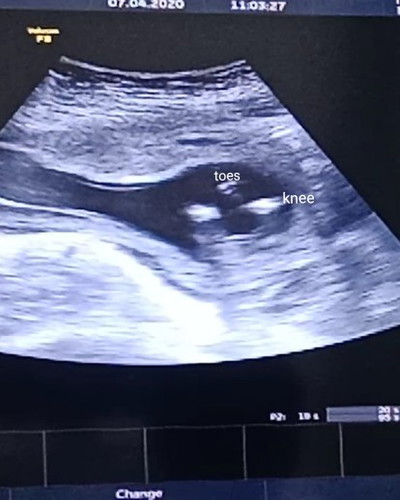

ท้องได้4 เดือนแล้วหมอบอกว่าเห็นเพศไม่ชัดค่อยมาซาวใหม่ตอนห้าเดือน แม่ๆช่วยดูให้หน่อยว่าน่าจะได้ลูกสาวหรือลูกชายค่ะ

รอดูก่อนก็ได้คะแม่ ภาพมองไม่ออกเลยคะ